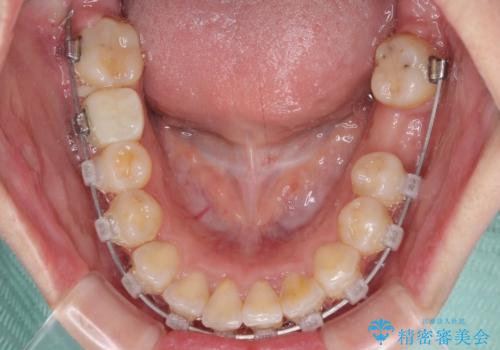

口元の突出感は少なく、下顎の叢生は軽微なものであったので、叢生の強い上顎左右の小臼歯を1本ずつ抜歯し、ワイヤー装置にて矯正治療を行うこととしました。

矯正治療を行う前に、根管治療の必要な上顎前歯と下顎大臼歯の根管治療を行い、矯正治療の途中で下顎の欠損部にインプラント埋入することとし、矯正治療後に補綴治療を行うこととしました。

矯正治療中にインプラント埋入を行うなど、余計な時間や無駄のない治療を行うことができました。